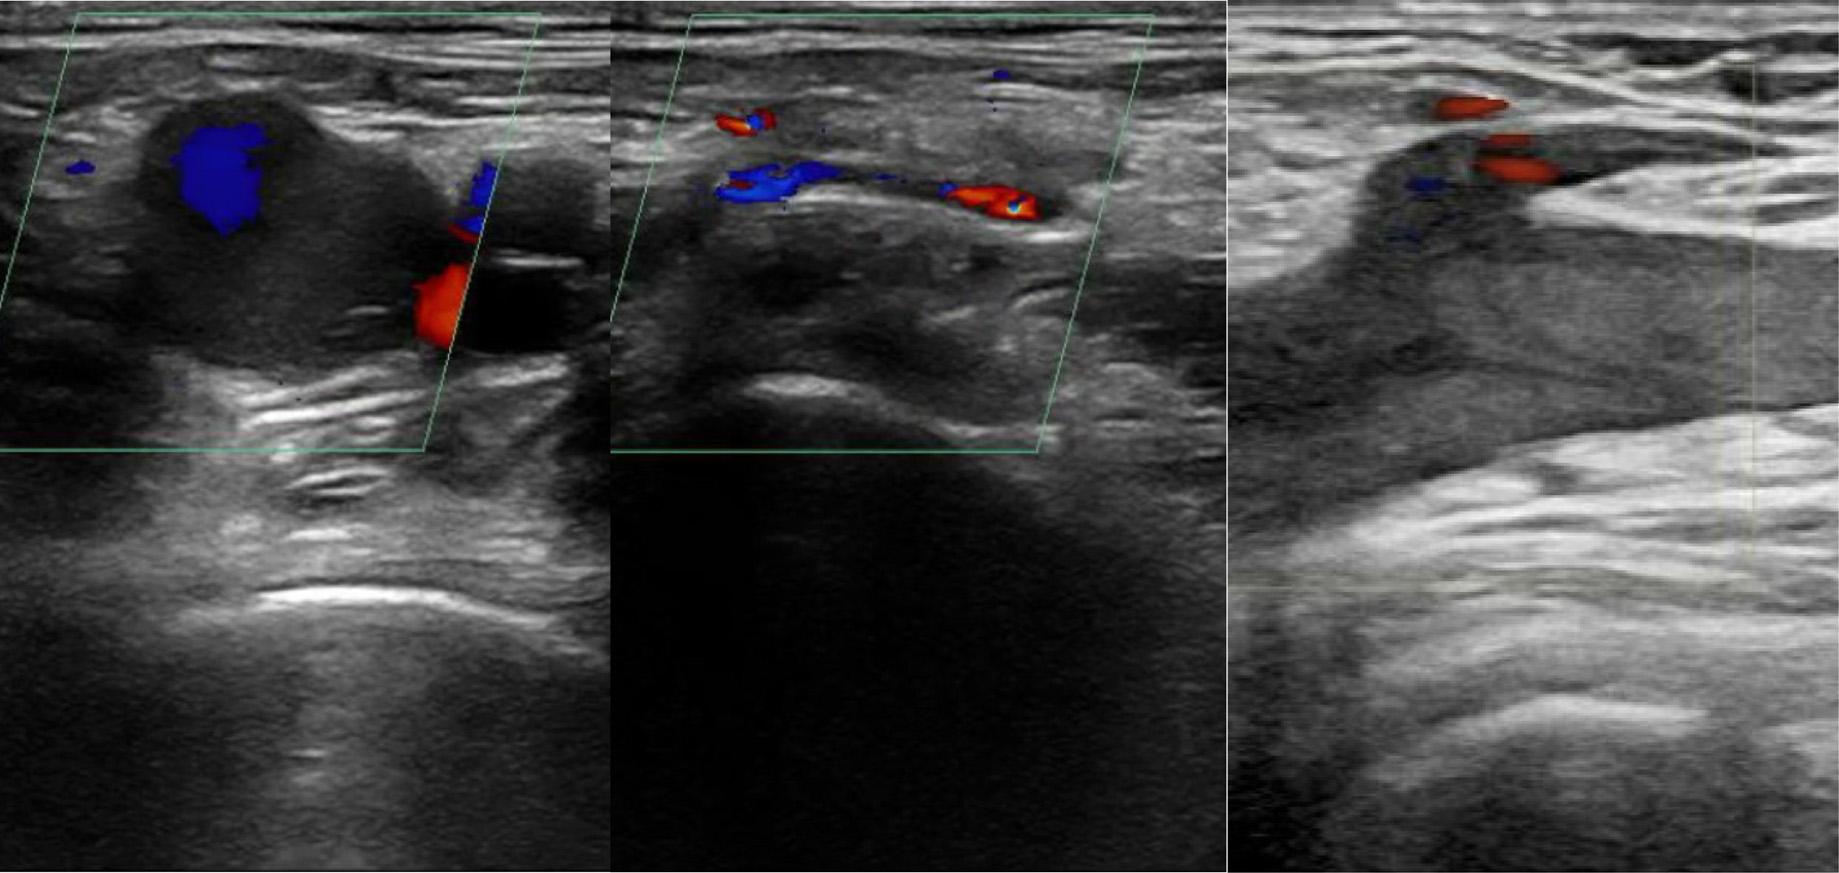

Hamzah M. Yusuf, Timothy Batchelor, Nicholas Ashenburg

298 Point-of-care Ultrasound Diagnosed Intraocular Breast Metastasis